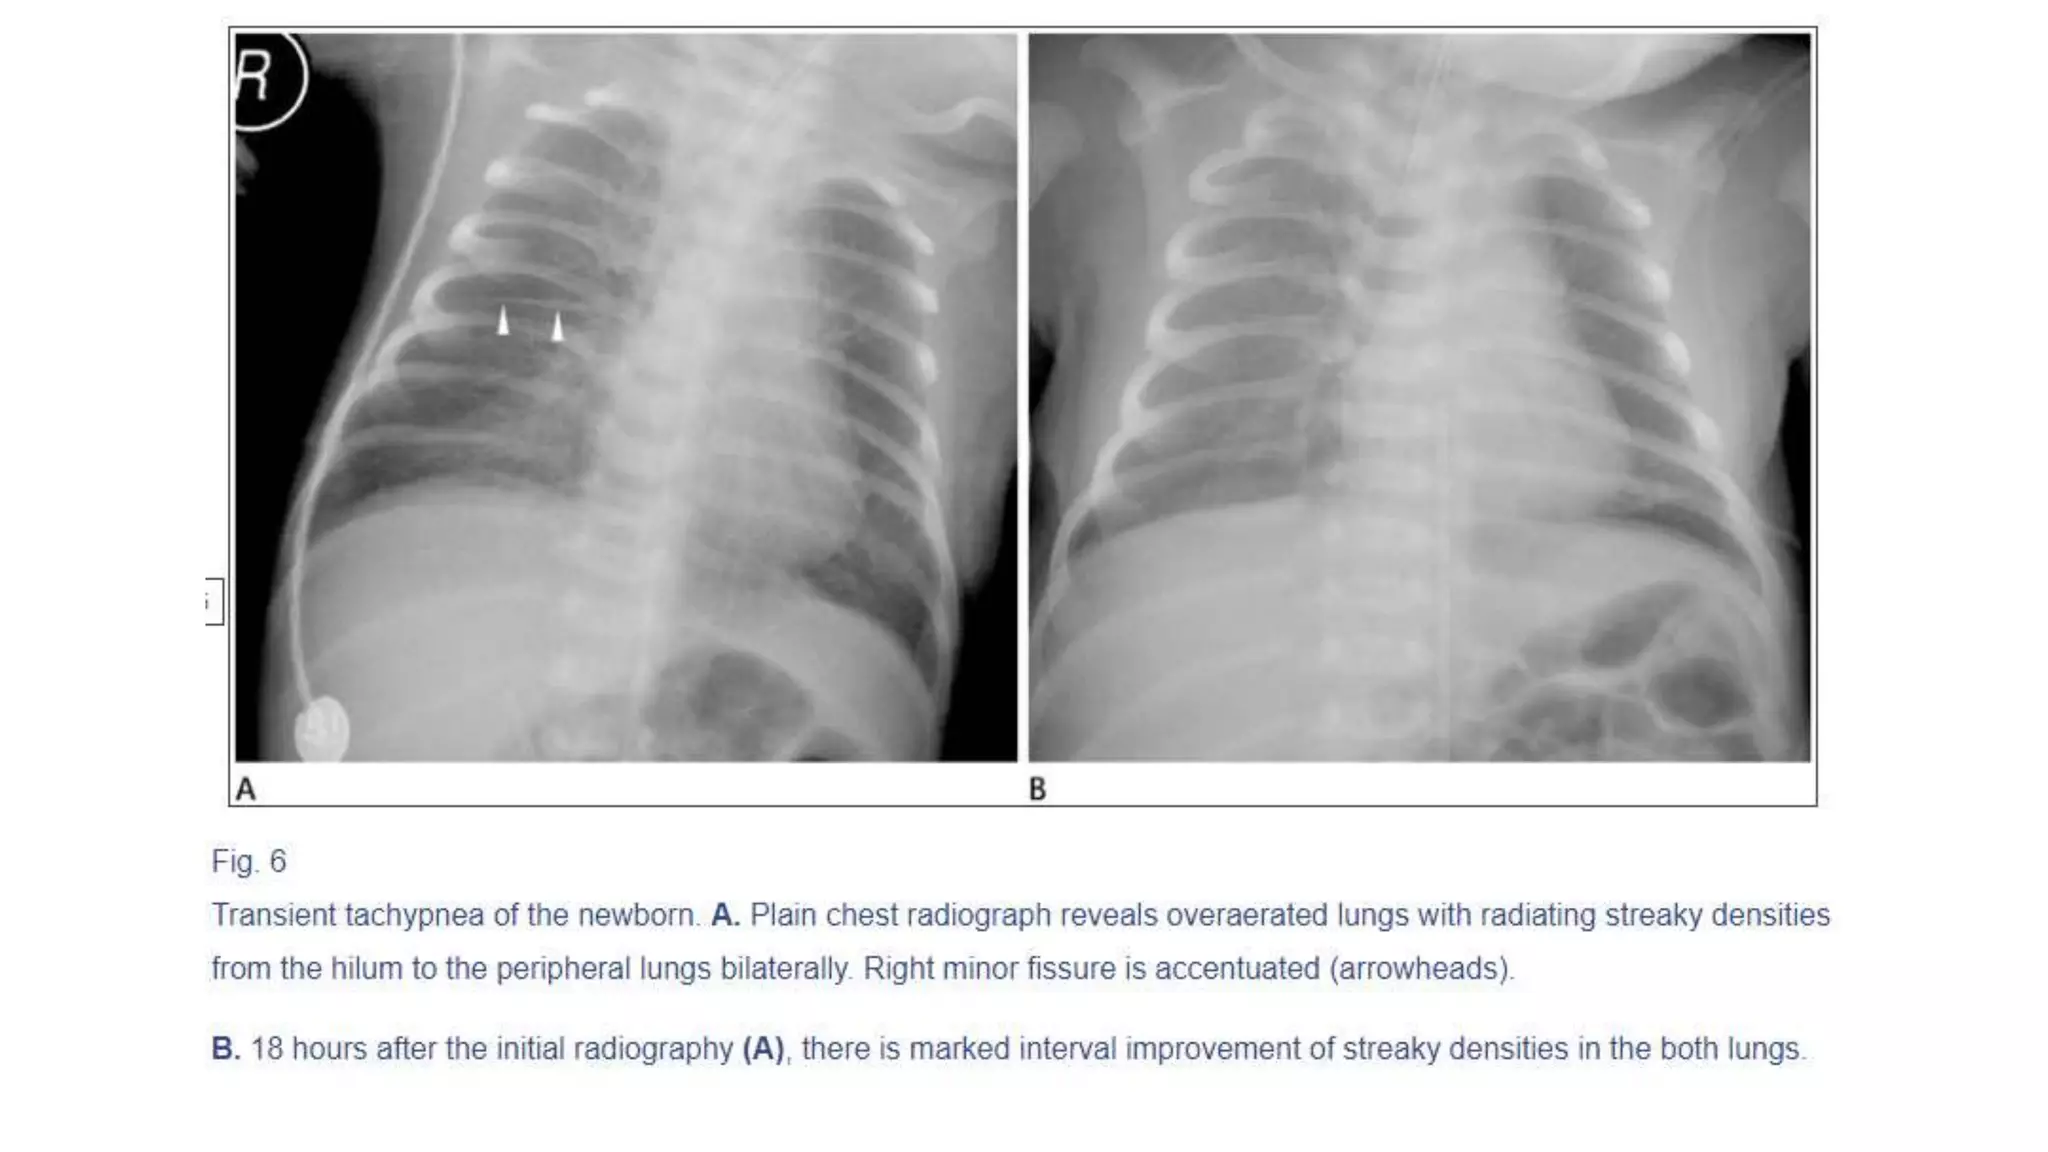

This document provides an overview of neonatal chest x-rays, including when they should and should not be performed, what a normal x-ray looks like, common positions of tubes and catheters, and common causes of respiratory distress in neonates. It discusses the appearance of a normal chest x-ray as well as conditions like respiratory distress syndrome, transient tachypnea of the newborn, meconium aspiration syndrome, and pneumonia. Surgical conditions like diaphragmatic hernia and esophageal atresia are also reviewed.